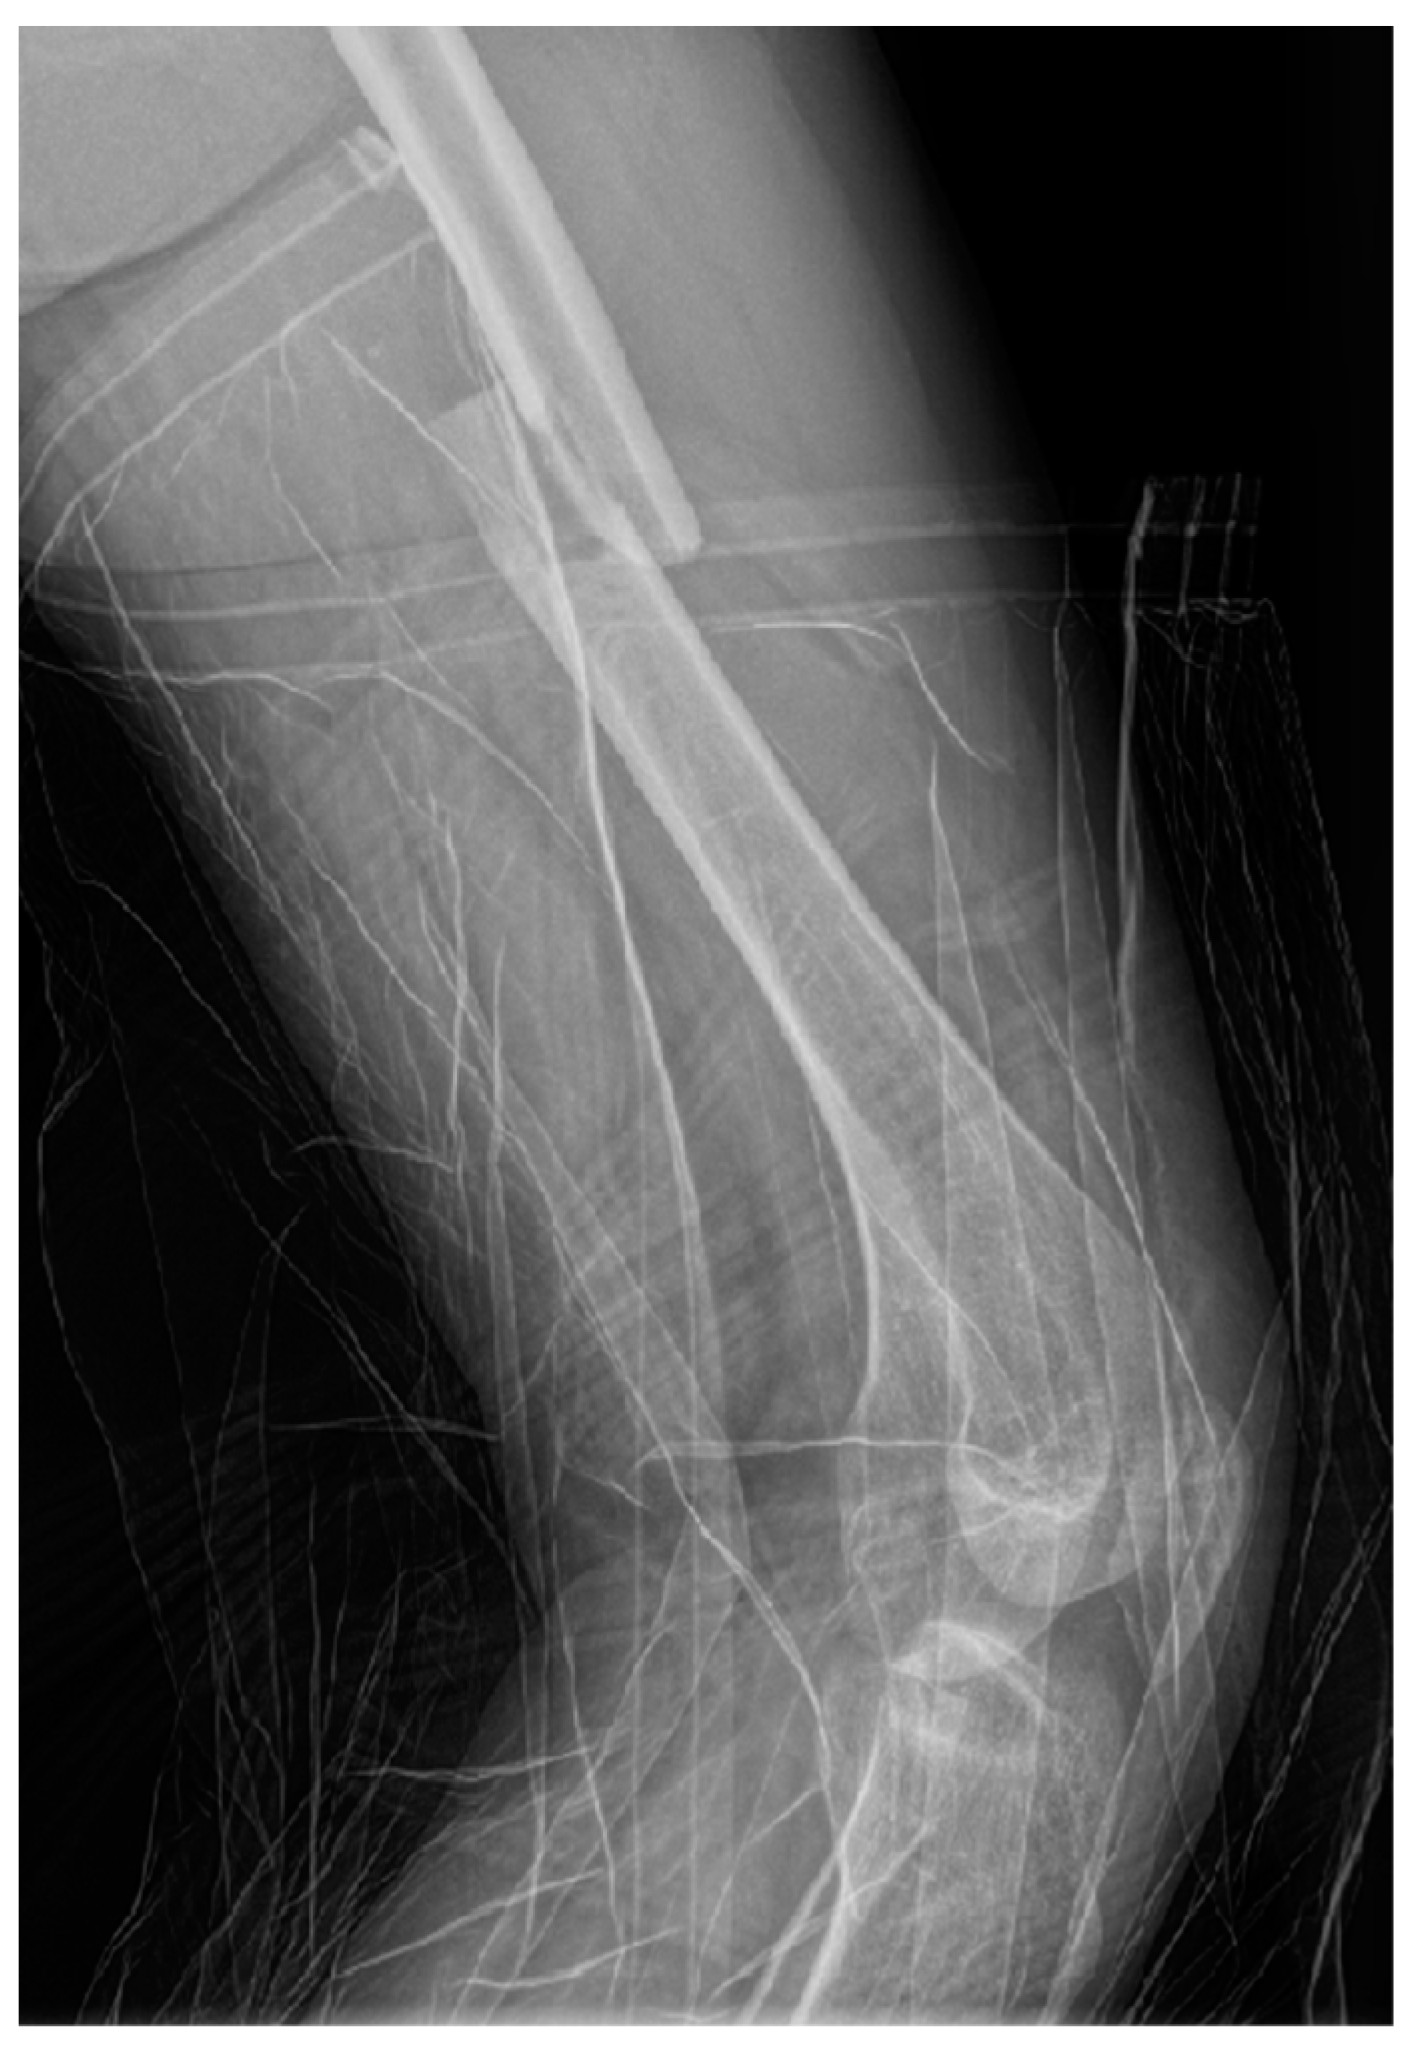

Radiographs (X-ray) of the left thigh were performed, under lead-apron protection on the abdominopelvic region, with the consent of the obstetrician. The radiation dose used during the X-ray was minimal. The total preoperative and intraoperative radiation dosage was 135.2 mGy. The diagnosis was a left mid-femoral diaphysis fracture with displacement (Figure 1).

Figure 1.

Profile X-ray of the left thigh revealing a fracture of the middle third of the femur with translation of the fragments.